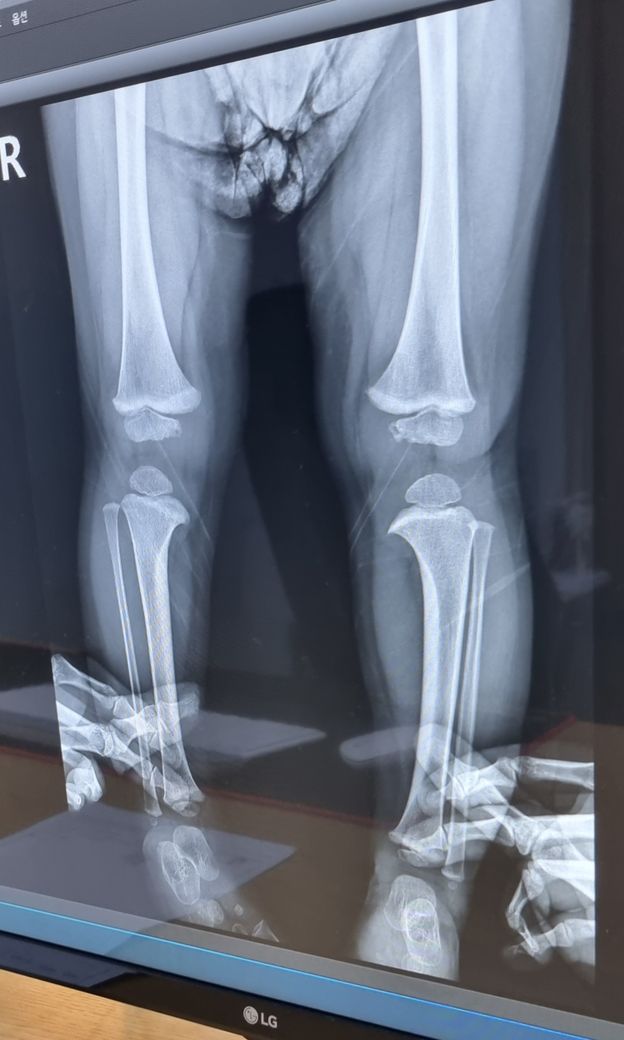

아기오다리.안장다리 교정 필요한가요?

22개월 남아인데..

어릴때부터 또래보단 다리가 오다리였어요.

안짱다리(Genu valgum)와 오다리(Genu Varus)는 무릎 관절을 기준으로 안쪽으로 또는 바깥쪽으로 각도가 휘어 있는 경우를 일컫는 용어입니다. 자세교정으로 어느정도 교정이 가능하지만 심한경우 수술을 하는 경우도 있습니다.